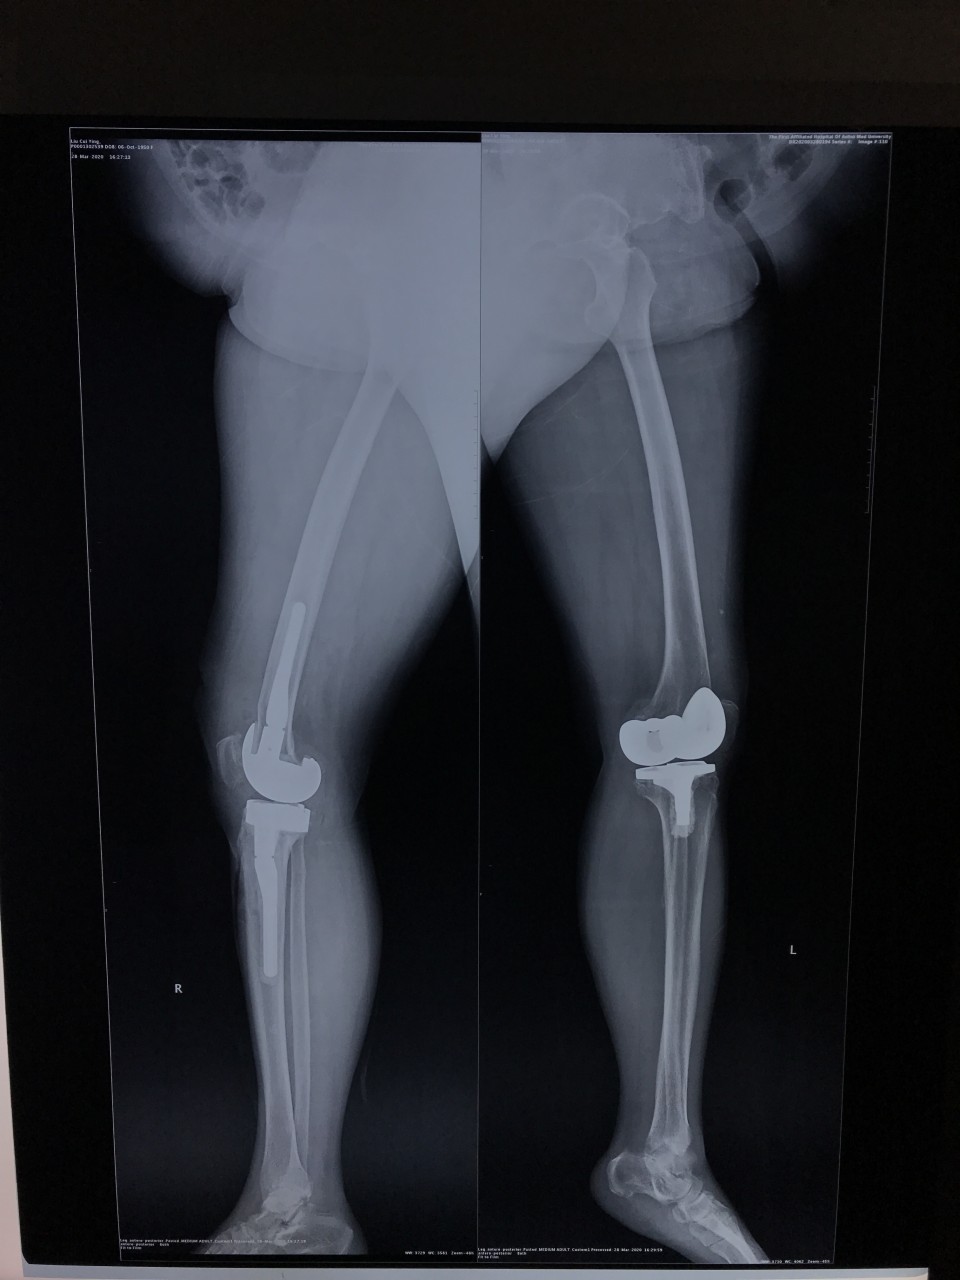

3月25日,一位69岁的女性患者因“右膝疼痛2年,加重伴活动受限1年”入院。术前摄片提示右侧膝关节假体松动。关节与显微修复外科胡孔足主任术前结合患者病史,体检及辅助检查,反复讨论,制定了精细的手术方案,术中假体安全取出,手术顺利。手术结束半小时,患者已经能够完全自主抬腿,屈曲。患者术后第二天下地正常行走。前后患者住院5天,快速康复出院。